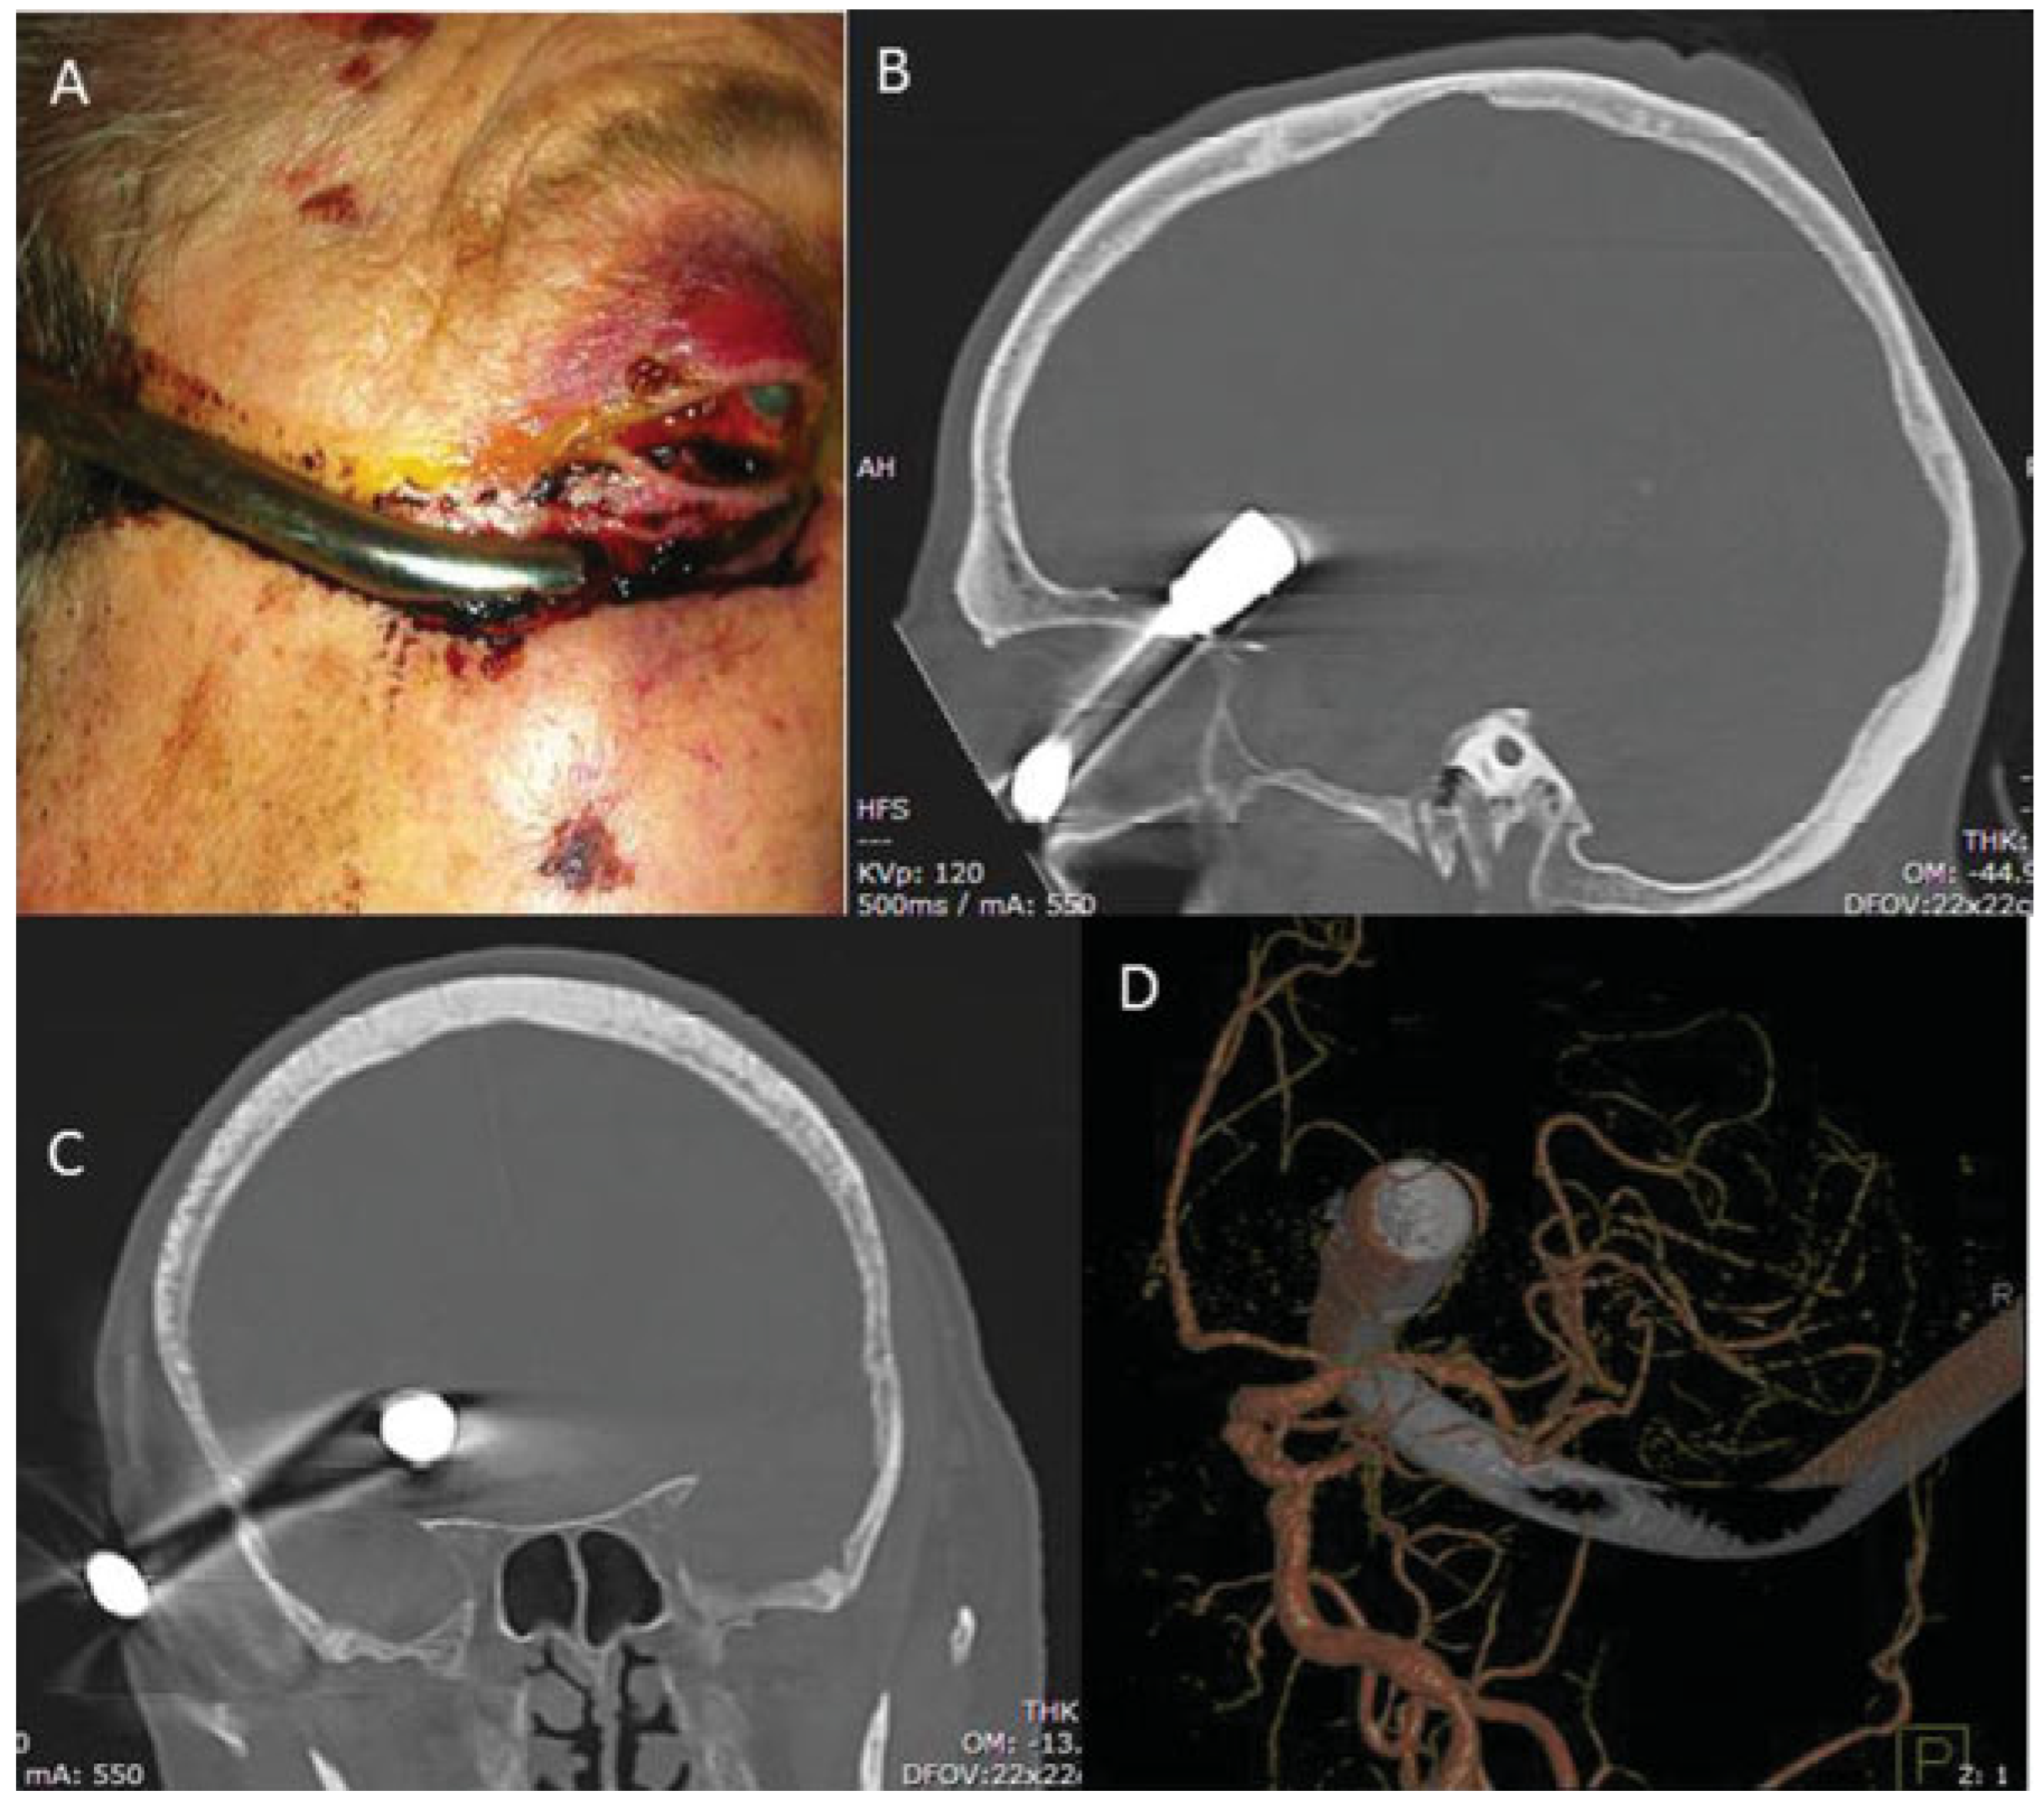

Extraction of Fronto-Orbital Shower Hook Through Transcranial Orbitotomy

:Case Report